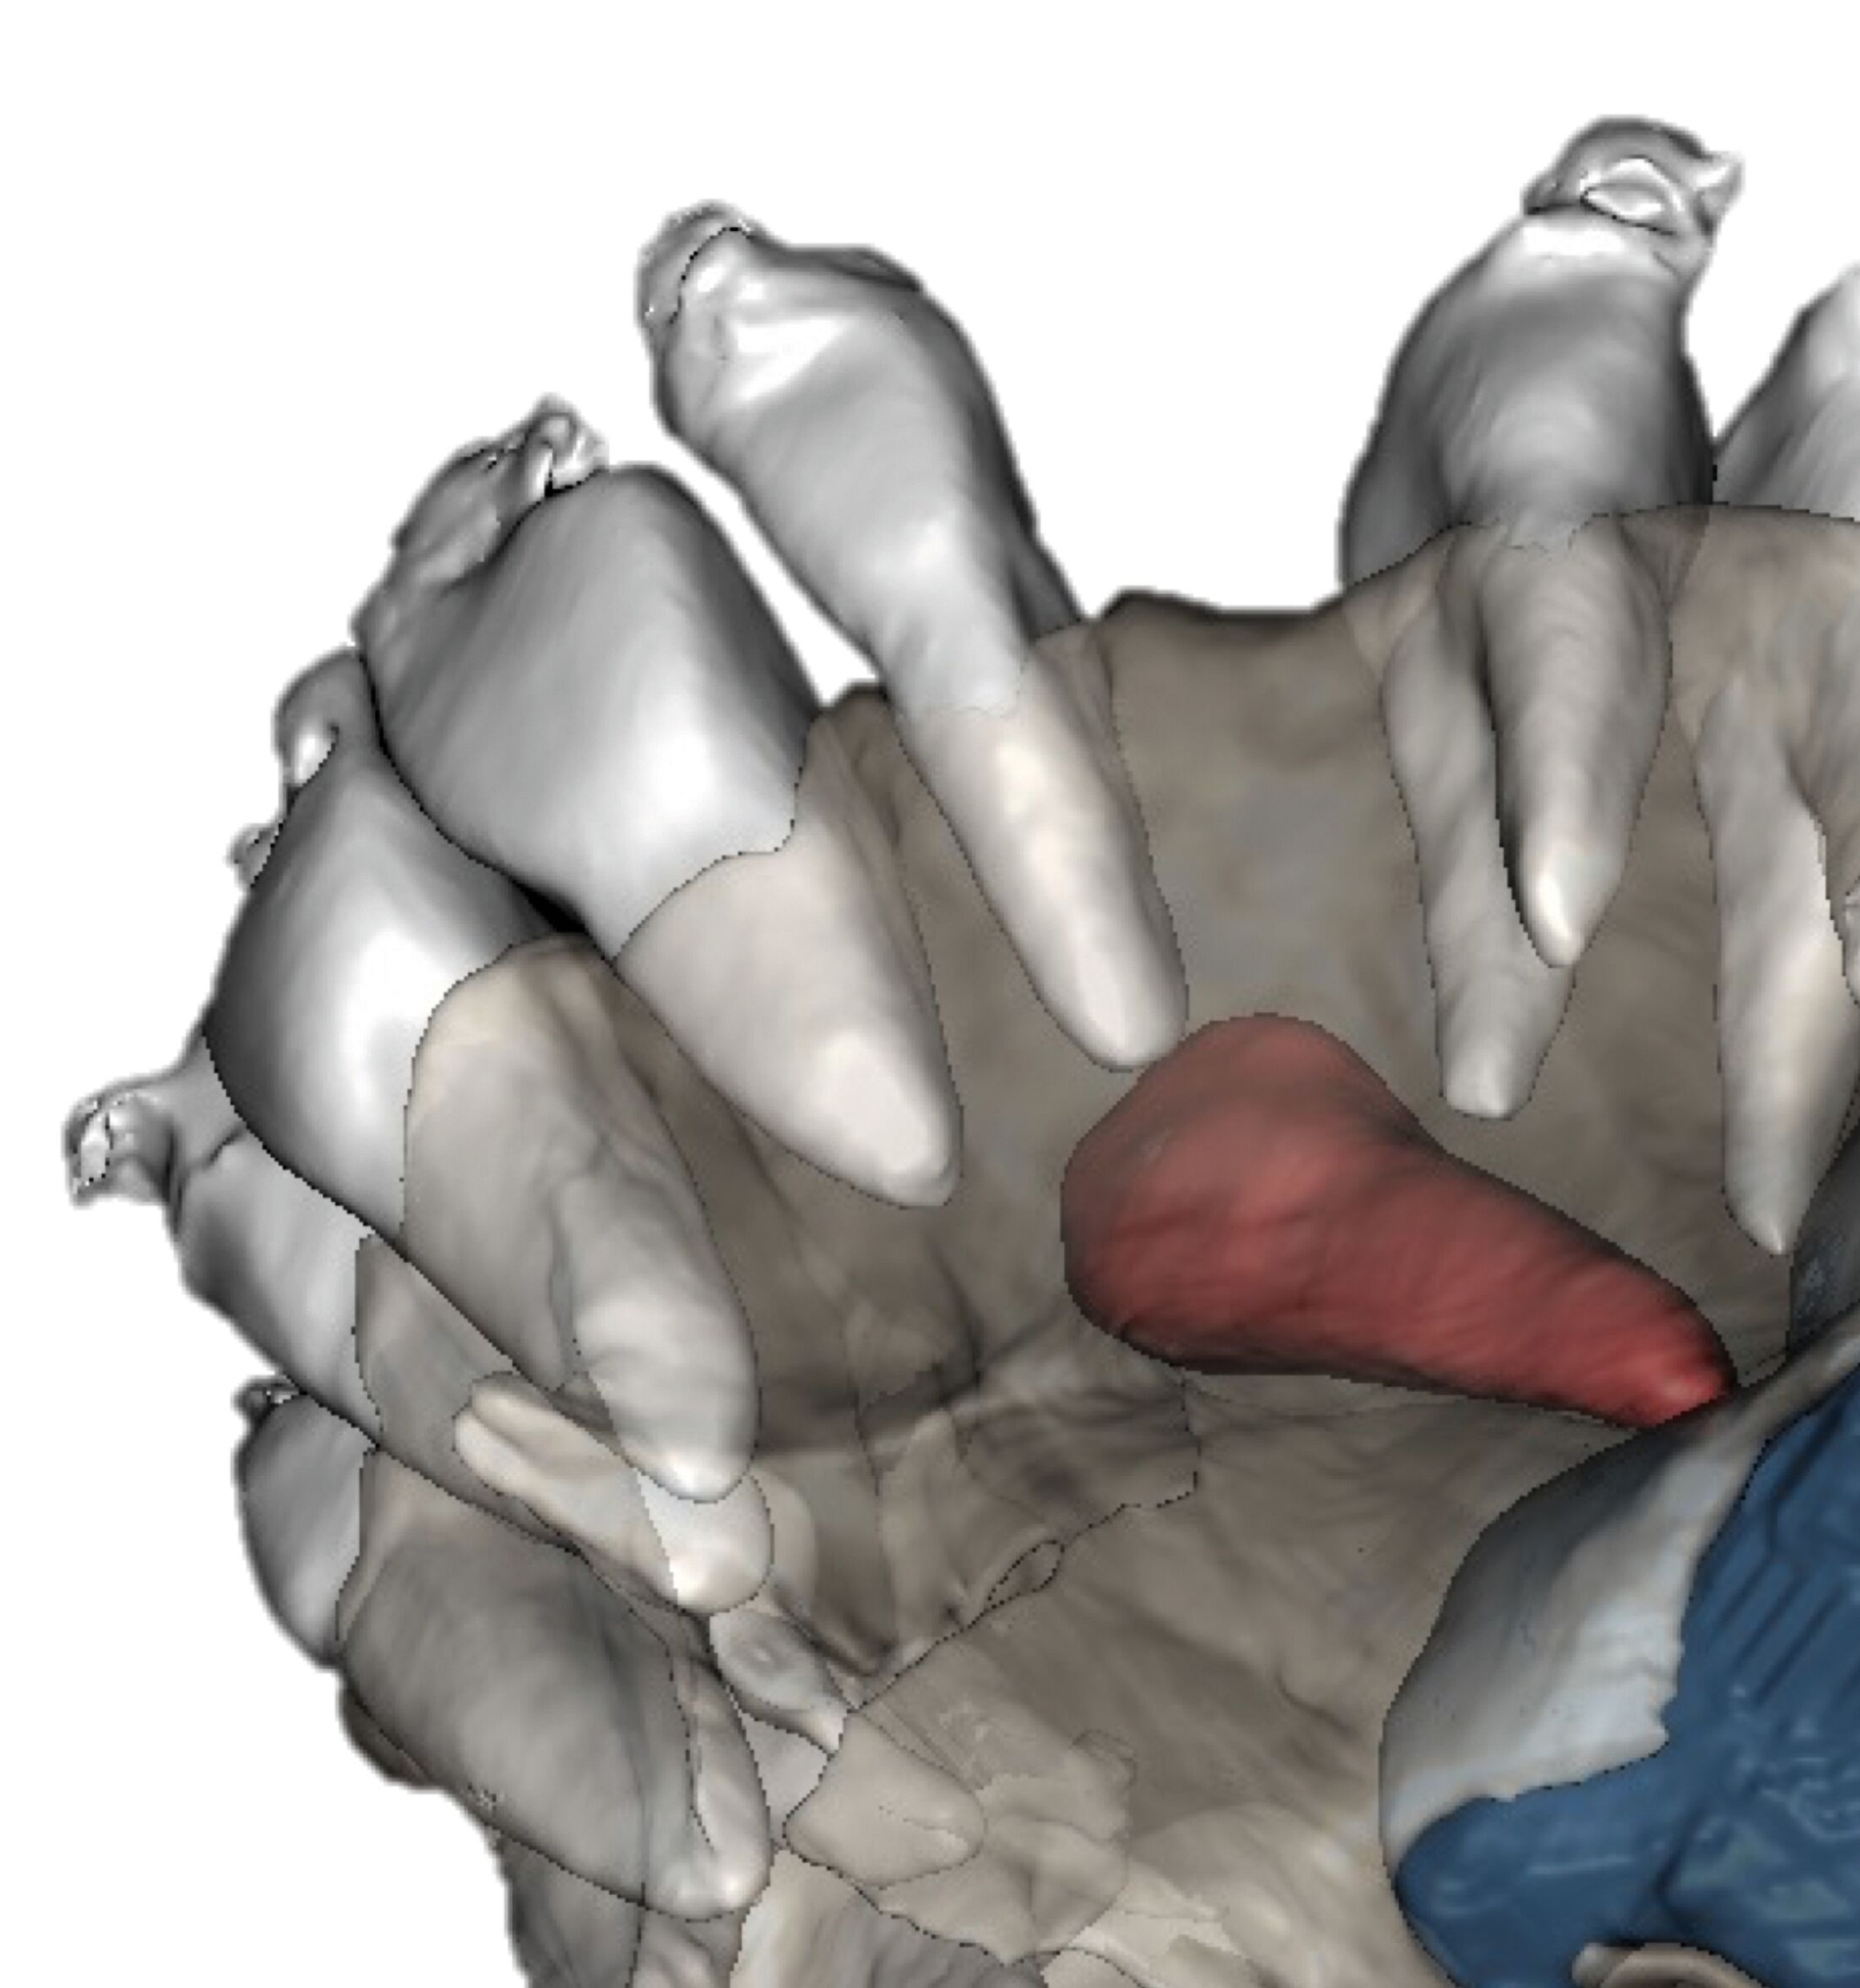

Anwendung findet der Metalldruck vor allem in der Herstellung skelettal verankerter Apparaturen, durch die reziproke Kräfte auf orthodontische Miniimplantate abgeleitet oder direkt skelettal aufgebracht werden können. Neben einer hohen Passgenauigkeit liegt der Vorteil vor allem in einer zielgerichteteren Therapie, die die anschließende oder zeitgleich durchgeführte Aligner- beziehungsweise Multibracket-Therapie verkürzt. Weiter können orthodontische Behandlungsaufgaben gelöst werden, die unter alleiniger Nutzung von Alignern beziehungsweise einer Multibracket-Apparatur deutlich limitiert wären. Beispiele beinhalten sogenannte „Mesialslider“ [Wilhelmy et al., 2022], „Distalslider“ [Graf et al., 2020] oder „Intrusionsapparaturen“.

Weiter erlauben hochindividuelle 3-D-gedruckte Designs die Therapie von skelettalen Fehlständen, beispielsweise in der Therapie defizitärer Maxillae [Pasqua et al., 2022; Bazargani et al., 2023; Ludwig et al., 2024] oder im Rahmen der nonoperativen oder postoperativen Prognathie-Behandlung [Hodecker et al., 2023]. Auch die Umsetzung skelettal verankerter Apparaturen mittels nichtmetallischer 3-D-Druckmaterialien findet in einzelnen Fällen Anwendung (Abbildung 3b). Zum Einbringen der Miniimplantate eignen sich sogenannte 3-D-gedruckte „Insertions-Guides“, die nach vorheriger digitaler Planung der Miniimplantat-Position, eine hochgenaue Insertion ermöglichen [Wilmes et al., 2022; Wilmes et al., 2022]. Die virtuelle Planung der Minischraubeninsertion ermöglicht eine sichere und nachvollziehbare Evaluation sämtlicher relevanter Gewebe, um die ohnehin geringen Risiken weiter zu minimieren. Zusätzlich kann man die Biomechanik der digital geplanten kieferorthopädischen Apparatur ideal koordinieren und – wenn man möchte – die Minischrauben und die Apparatur in einer Sitzung einsetzen.